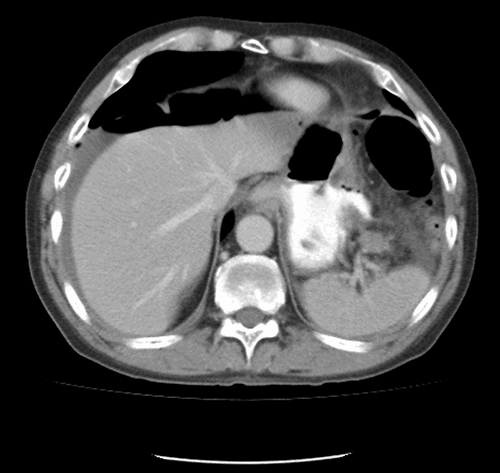

On postpartum day five, the patient returned to the ED with signs of sepsis and multiple organ failure. She was complaining of severe abdominal pain that had been progressively worsening for five days, nausea and vomiting, subjective fever, chills, sore throat, dyspnea, chest pain, palpitations, weakness, diffuse muscle cramps and lower leg edema. Her last BM was on the day of readmission, it was liquid and unclear if it was bloody because of postpartum vaginal bleeding. Her labs were unremarkable except for a leukocytosis of nineteen and renal failure with a BUN of 54 and creatinine of 2.7. On examination, the patient appeared very fatigued and drowsy, tachycardia was noted with a regular rhythm. The abdomen was grossly distended, diffusely tender with rebound and guarding. There were hypoactive bowel sounds and tympany present. The rest of the physical exam was unremarkable. Abdominal CT scan showed pneumoperitoneum.

Figure 1. CT scan of abdomen done in ED on admission.